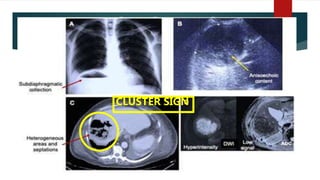

 The cluster sign is characteristic of the PHA, consisting of

several lesions grouping to form a single multiloculated cavity.

CLUSTER SIGN

(CLUSTER SIGN)